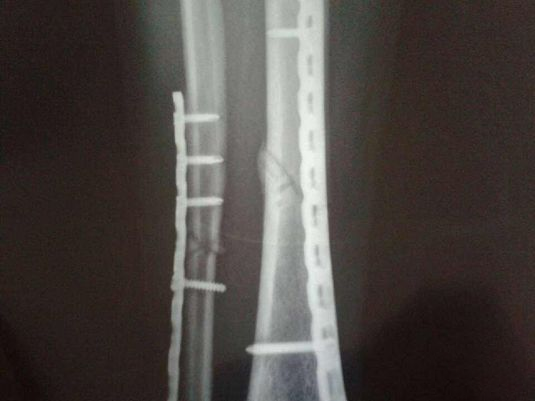

1、胫腓骨干双骨折

4、前者最常见,由于所受暴力大,骨和软组织损伤重,并发症多,治疗较困难。后两者少见,常因直接暴力引起,移位少,预后较好。

②手术治疗:分为切开复位内固定和支架外固定。适用于胫骨横形骨折、斜形骨折或螺旋形骨折.

钢板螺钉内固定

适用于各种类型的胫骨干骨折,尤以多段粉碎骨折效果好,但要求设备齐全。

髓内针内固定

无论闭合性或开放性小腿骨折均适用,尤其是后者,更具有适用价值。